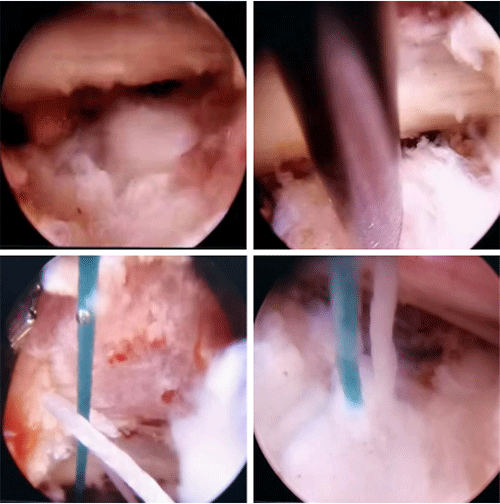

针对患者年纪轻需要尽量保留活动节段的情况,崔新刚教授确定为患者实施OBE内镜下髓核摘除术,去除椎间盘突出髓核解除疼痛。同时,因患者体重较大,髓核摘除术后突出复发风险要高于其他人。崔新刚教授决定在OBE内镜下髓核摘除后行纤维环缝合术,降低患者术后复发风险。仅用时不足1小时,崔新刚教授顺利完成OBE髓核摘除术+纤维环缝合术。术后患者疼痛解除。

脊柱外科崔新刚教授基于6000余例椎间孔镜手术经验首创具有完全自主知识产权的单孔双介质内镜技术(OBE),实现气水双介质和内镜技术完美结合,具有视野清晰、适应证广的特点。纤维环缝合术是治疗腰椎间盘突出症的一项新兴技术。在崔新刚教授带领下,两项技术的完美融合进一步推动了脊柱内镜事业的发展,提高了我院脊柱外科疾病综合诊疗水平,以更加安全、更加微创的优质技术服务群众。